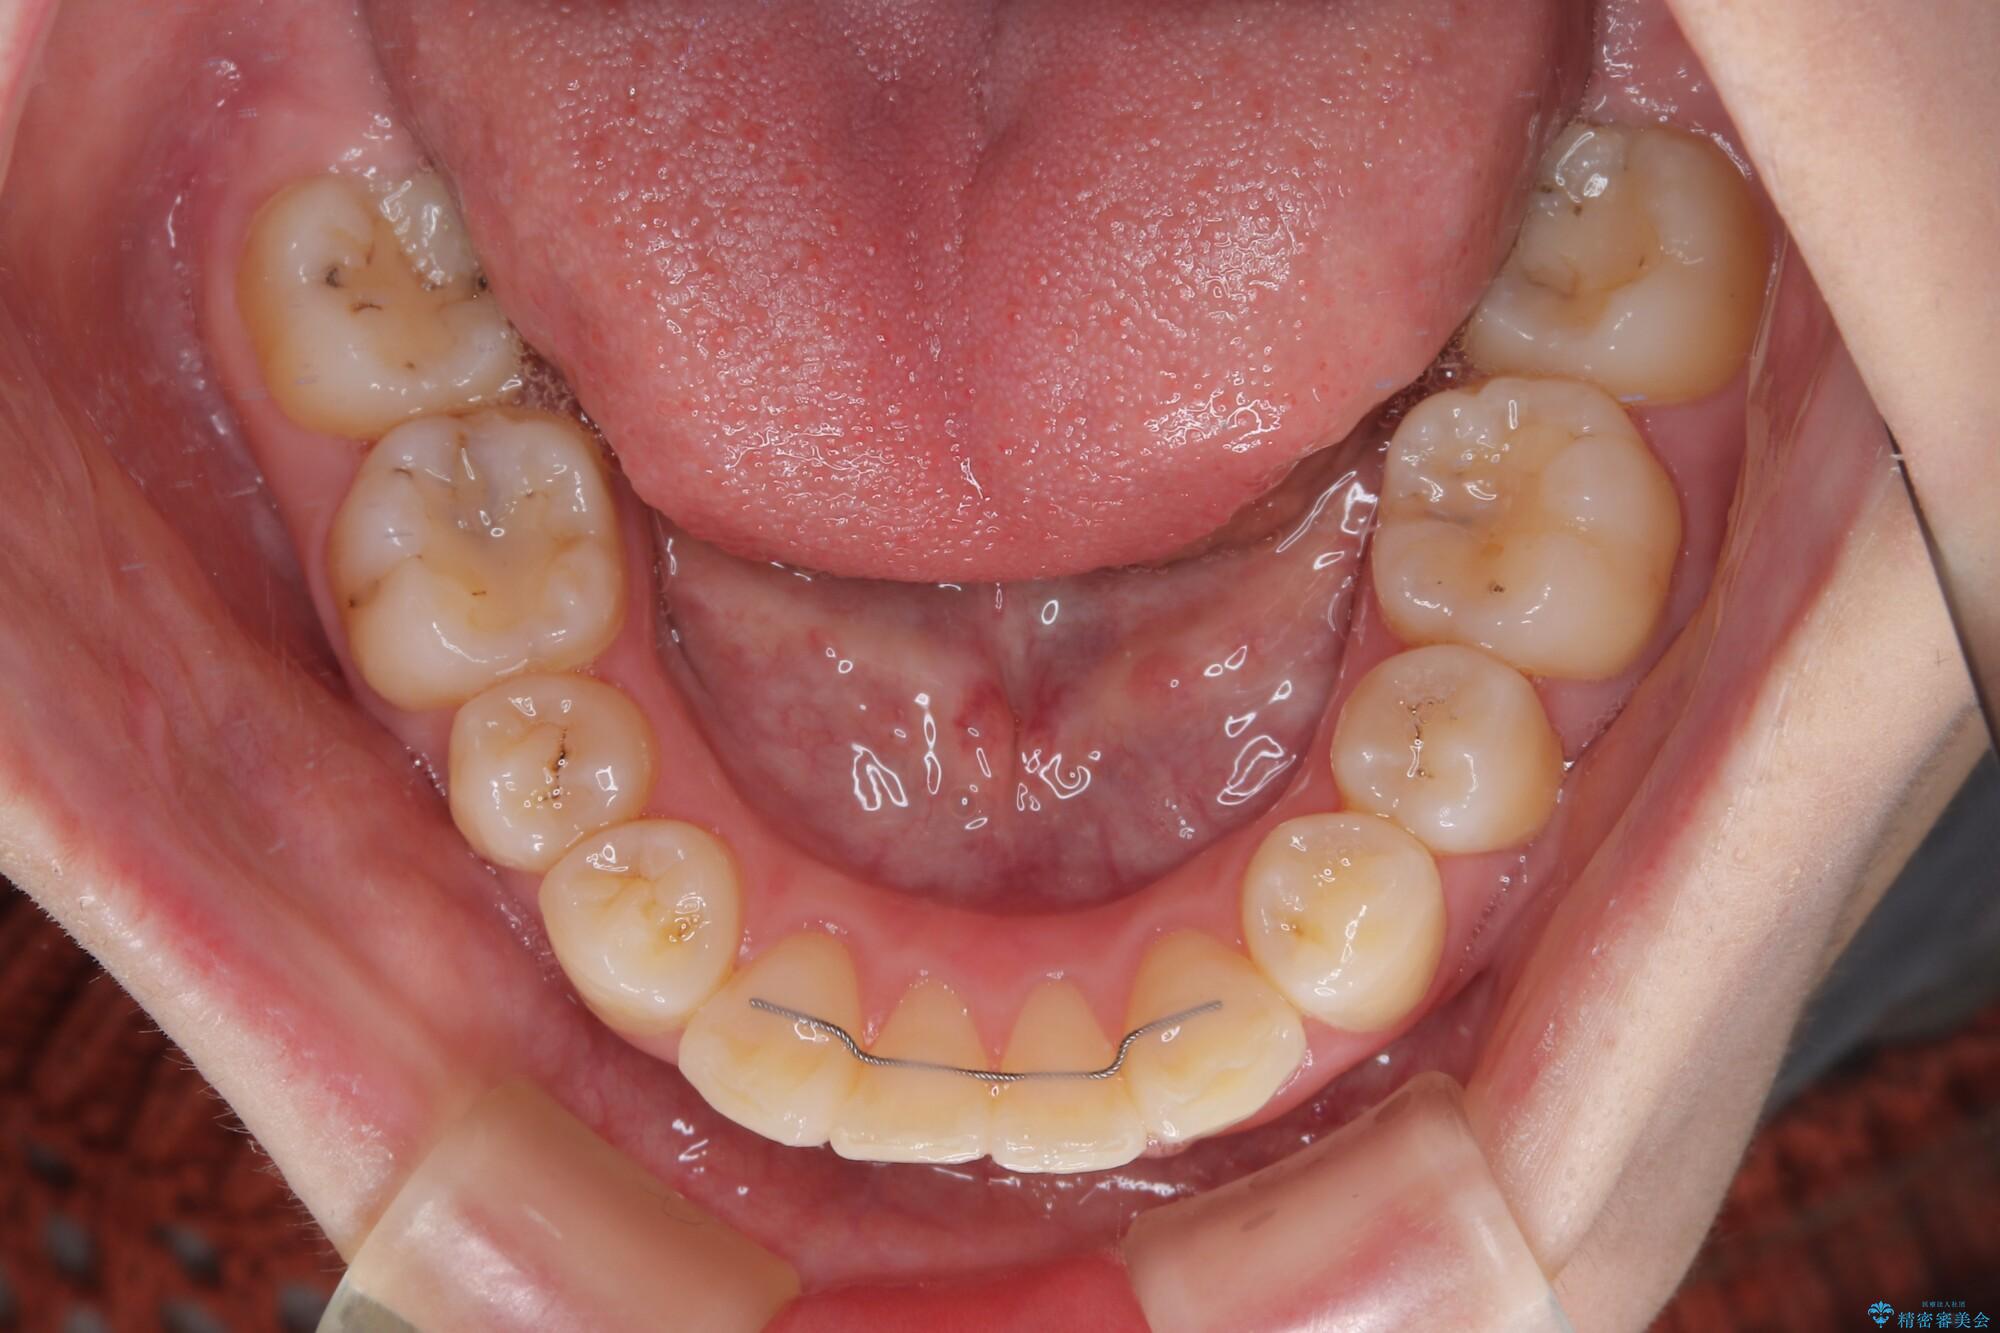

- 飛び出した上顎前歯を気にして来院された患者様です。

下顎は左右2番目の歯が2本欠損しており、上下前歯の前後的な位置は著しくずれている状態でした。

骨格的にも上顎骨が前突傾向にあり、極端な過蓋咬合になっていました。

強い咬合力に抵抗するように歯を動かす必要があるにもかかわらず、上顎第一大臼歯が1本欠損しているため、治療は困難を極めることが予想されました。

上顎前突を改善するために上顎左右第一小臼歯を抜歯し、補助装置を用いて上顎臼歯が前方に移動しないように工夫しながら、表側のワイヤー装置にて歯列を整えていくこととしました。

矯正治療後には、上顎欠損部をオールセラミックブリッジにて補綴治療を行うこととしました。